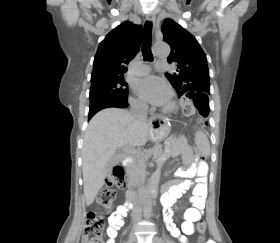

Remitida para valoración de masa pulmonar izquierda detectada en una RX de torax

caso 12-09-03 (FMC)

varón de 30 años con historia de tos y disnea de varios meses de evolución